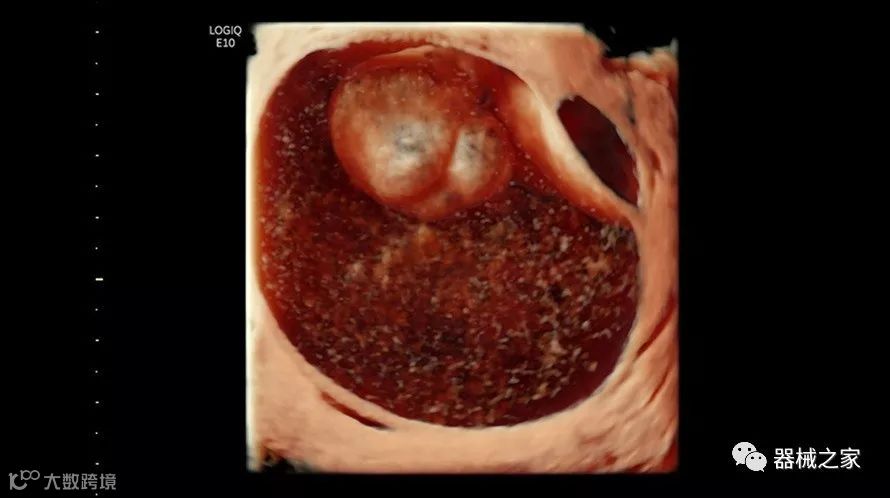

2018年发布的另一个例子是飞利浦的TrueVue,它提供照片般逼真的渲染,并能够在三维超声图像上改变光源的位置。它允许用户改变照明条件以提高对比度。可以移动光源以改变阴影并增加更多深度感知。还可以推动光源穿过组织以对解剖结构进行背光。